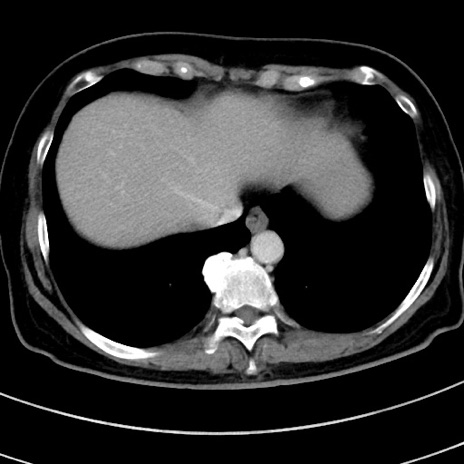

症例

冠状断像